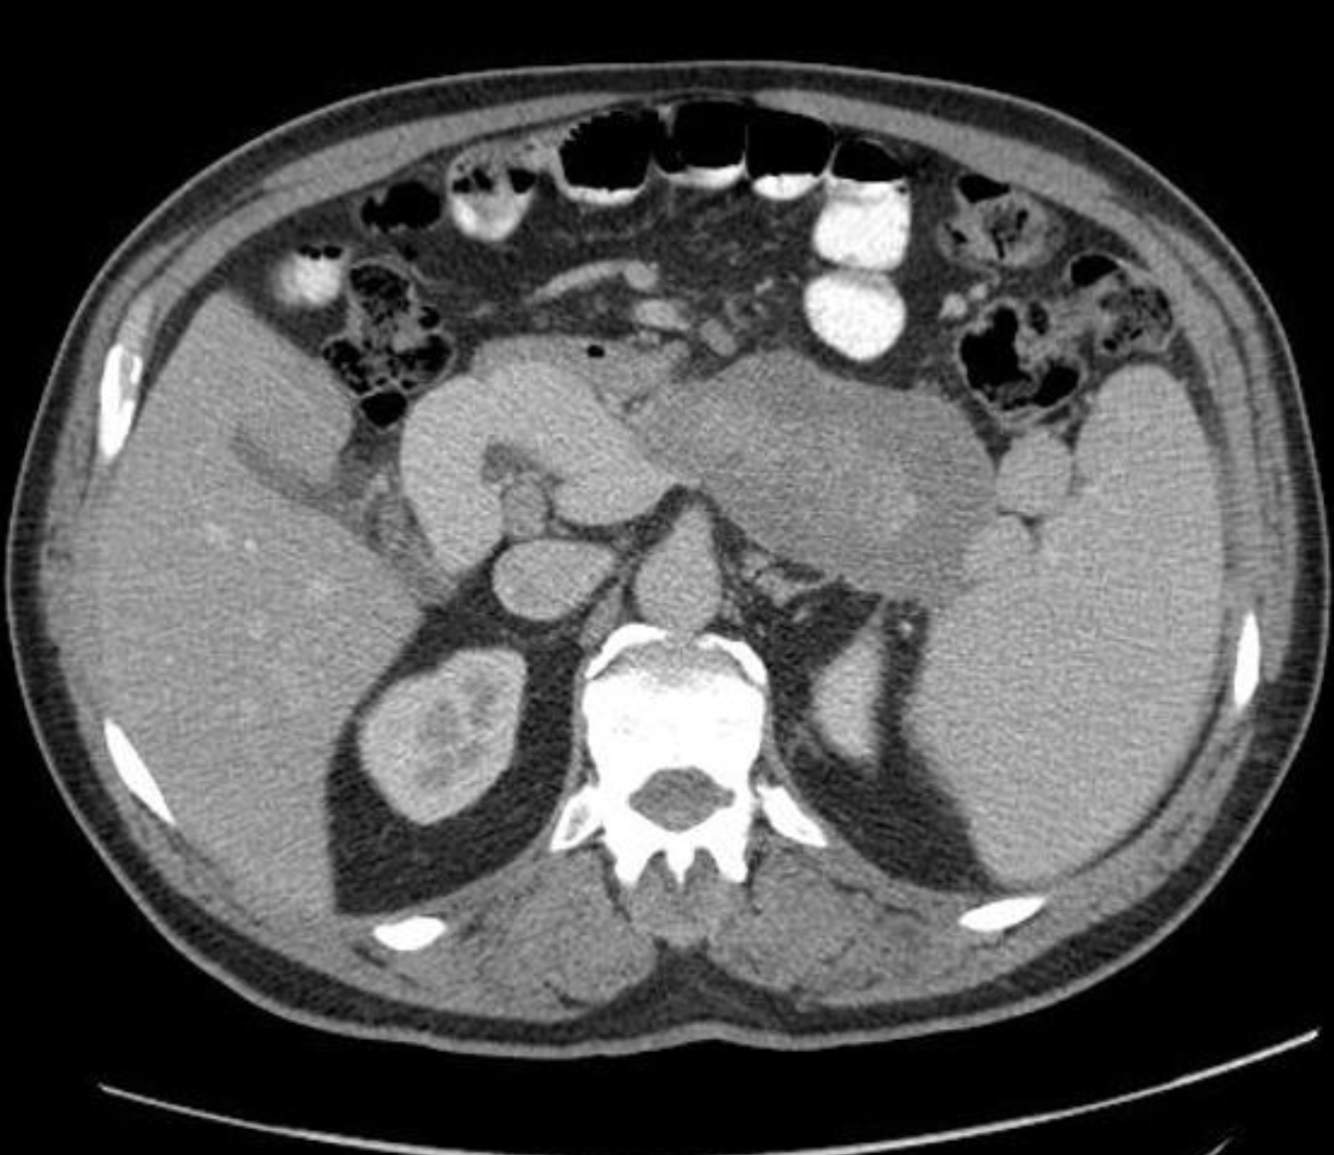

Generalised atrophy of body and tail of the pancreas. Diffuse parenchymal calcification with main pancreatic duct dilated throughout its course with a beaded appearance reaching up to 10mm in diameter. Multiple intraductal calculi are present, the largest measuring 10 mm in the pancreatic head. This stone is obstructing the main pancreatic duct resulting in ductal dilatation. No hypoenhancing pancreatic parenchymal lesions. No peripancreatic fat stranding or localised collections. No radio-opaque stones in the gallbladder, cystic duct, or common bile duct. No intrahepatic biliary duct dilatation.

Case Discussion

When presenting with an episode of abdominal pain, this patient underwent an ultrasound of the abdomen which revealed features of chronic calcific pancreatitis. However, due to the suboptimal acoustic window, a CT scan was recommended to rule out any pancreatic inflammation or neoplasm. The chronic inflammatory changes result in reduction in volume of pancreatic parenchyma with only a ghost of the gland remaining in the latter stages. These patients are more prone for neoplasms and have to be watched closely.